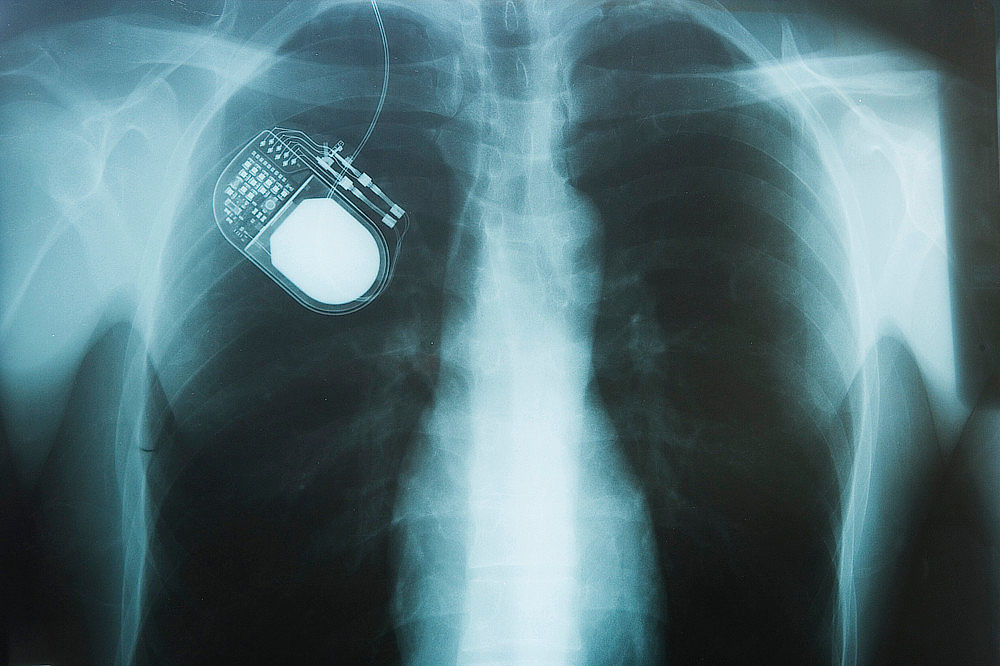

Pokud se v průběhu onemocnění objeví silné výkyvy účinnosti léčby nebo motorické komplikace, které vedou k výraznému zhoršení kvality života, může přicházet v úvahu chirurgická léčba. Takzvaná hluboká mozková stimulace [3, 4] spočívá v tom, že během chirurgického zákroku jsou vsazeny elektrody do konkrétních oblastí mozku, které jsou onemocněním postiženy. Tyto elektrody jsou propojeny s neurostimulátorem, který je implantován pod klíční kost. Slabé proudové impulzy pak v postižených oblastech mozku vyvolávají elektrické dráždění, a tím pozitivně ovlivňují narušenou aktivitu těchto oblastí.

U pacientů, jejichž zdravotní stav umožňuje tento zákrok, může hluboká mozková stimulace výrazně zmírnit obzvláště tři motorické hlavní příznaky, tzn. poruchy hybnosti (bradykineze, hypokineze, akineze), svalovou ztuhlost (rigidita) a klidový třes (tremor), a také OFF-stavy. Hlavní výhoda této metody spočívá v tom, že účinek je trvalý (24 hodin denně) a že lze výrazně snížit dávku užívaných léků. Hluboká mozková stimulace se obvykle užívá u pacientů mladších 70 let.

Obrázek 2: Na rentgenovém snímku je vidět neurostimulátor, který je implantován pod pacientovou klíční kostí. (Zdroj: depositphotos.com)